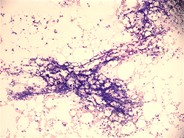

32+ Acquired Aplastic Anemia Causes Images. Red blood cells, white blood cells, and platelets. Bone marrow is the spongy.

Blood cells are produced in the bone marrow by stem cells that reside there. Mcv is usually increased in aplastic anemia. Acquired aplastic anemia is usually considered an autoimmune disease. Red blood cells, white blood cells.